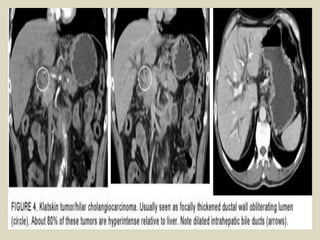

Hilar cholangiocarcinoma The most common

location for cholangiocarcinoma is either at the

confluence of the right and left hepatic ducts, or at

the proximal CHD, and has been termed a ''Klatskin

tumor.'' These tumors can be small and difficult to

visualize early at imaging. Hilar

cholangiocarcinoma can usually be differentiated

from adjacent adenopathy or extrinsic masses

causing biliary obstruction due to the latter

causing compression and displacement of the duct.

Klatskin tumor (hilar cholangiocarcinoma).